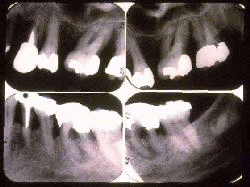

Los Rayos X de los dientes izquierdos en el mismo paciente. Aproximadamente se ha perdido el 50% del hueso alveolar. En distal de canino y en  los primeros premolares han perdido 2/3 del hueso alveolar. En los  molares la destrucción del hueso parece acercarse a apical y las raíces muestran signos de lesión de furcación en el primer y segundo molar superior e inferior. Los rasgos radiográficos no permiten un análisis detallado de la anatomía de la destrucción periodontal.